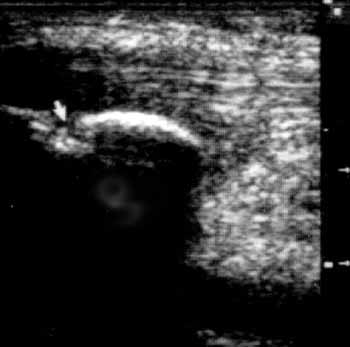

Рис. 1. Область надколенника, сагиттальная проекция; перелом надколенника

(стрелка).